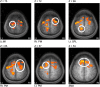

Repetitive brain stimulation protocols induce plasticity in the stimulated site in brain slice models. Recent evidence from network models has indicated that additional plasticity-related changes occur in nonstimulated remote regions. Despite increasing use of brain stimulation protocols in experimental and clinical settings, the neural substrates underlying the additional effects in remote regions are unknown. Diffusion-weighted MRI (DWI) probes water diffusion and can be used to estimate morphological changes in cortical tissue that occur with the induction of plasticity. Using DWI techniques, we estimated morphological changes induced by application of repetitive transcranial magnetic stimulation (rTMS) over the left primary motor cortex (M1). We found that rTMS altered water diffusion in multiple regions including the left M1. Notably, the change in water diffusion was retained longest in the left M1 and remote regions that had a correlation of baseline fluctuations in water diffusion before rTMS. We conclude that synchronization of water diffusion at rest between stimulated and remote regions ensures retention of rTMS-induced changes in water diffusion in remote regions. Synchronized fluctuations in the morphology of cortical microstructures between stimulated and remote regions might identify networks that allow retention of plasticity-related morphological changes in multiple regions after brain stimulation protocols. These results increase our understanding of the effects of brain stimulation-induced plasticity on multiregional brain networks. DWI techniques could provide a tool to evaluate treatment effects of brain stimulation protocols in patients with brain disorders.